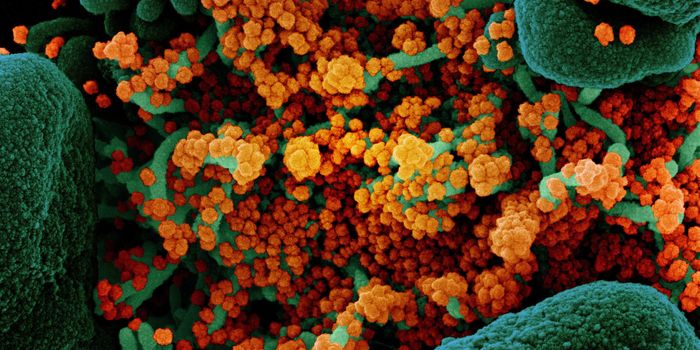

SEP 25, 2021Health & MedicineAfter a year-long study, researchers have assembled a detailed narrative about how the SARS-Cov-2 virus has spread on th ...